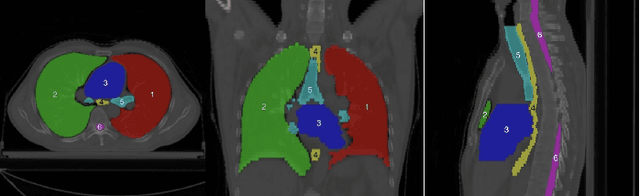

Abstract:The task of labeling multiple organs for segmentation is a complex and time-consuming process, resulting in a scarcity of comprehensively labeled multi-organ datasets while the emergence of numerous partially labeled datasets. Current methods are inadequate in effectively utilizing the supervised information available from these datasets, thereby impeding the progress in improving the segmentation accuracy. This paper proposes a two-stage multi-organ segmentation method based on mutual learning, aiming to improve multi-organ segmentation performance by complementing information among partially labeled datasets. In the first stage, each partial-organ segmentation model utilizes the non-overlapping organ labels from different datasets and the distinct organ features extracted by different models, introducing additional mutual difference learning to generate higher quality pseudo labels for unlabeled organs. In the second stage, each full-organ segmentation model is supervised by fully labeled datasets with pseudo labels and leverages true labels from other datasets, while dynamically sharing accurate features across different models, introducing additional mutual similarity learning to enhance multi-organ segmentation performance. Extensive experiments were conducted on nine datasets that included the head and neck, chest, abdomen, and pelvis. The results indicate that our method has achieved SOTA performance in segmentation tasks that rely on partial labels, and the ablation studies have thoroughly confirmed the efficacy of the mutual learning mechanism.

Abstract:Accurate segmentation of multiple organs of the head, neck, chest, and abdomen from medical images is an essential step in computer-aided diagnosis, surgical navigation, and radiation therapy. In the past few years, with a data-driven feature extraction approach and end-to-end training, automatic deep learning-based multi-organ segmentation method has far outperformed traditional methods and become a new research topic. This review systematically summarizes the latest research in this field. For the first time, from the perspective of full and imperfect annotation, we comprehensively compile 161 studies on deep learning-based multi-organ segmentation in multiple regions such as the head and neck, chest, and abdomen, containing a total of 214 related references. The method based on full annotation summarizes the existing methods from four aspects: network architecture, network dimension, network dedicated modules, and network loss function. The method based on imperfect annotation summarizes the existing methods from two aspects: weak annotation-based methods and semi annotation-based methods. We also summarize frequently used datasets for multi-organ segmentation and discuss new challenges and new research trends in this field.